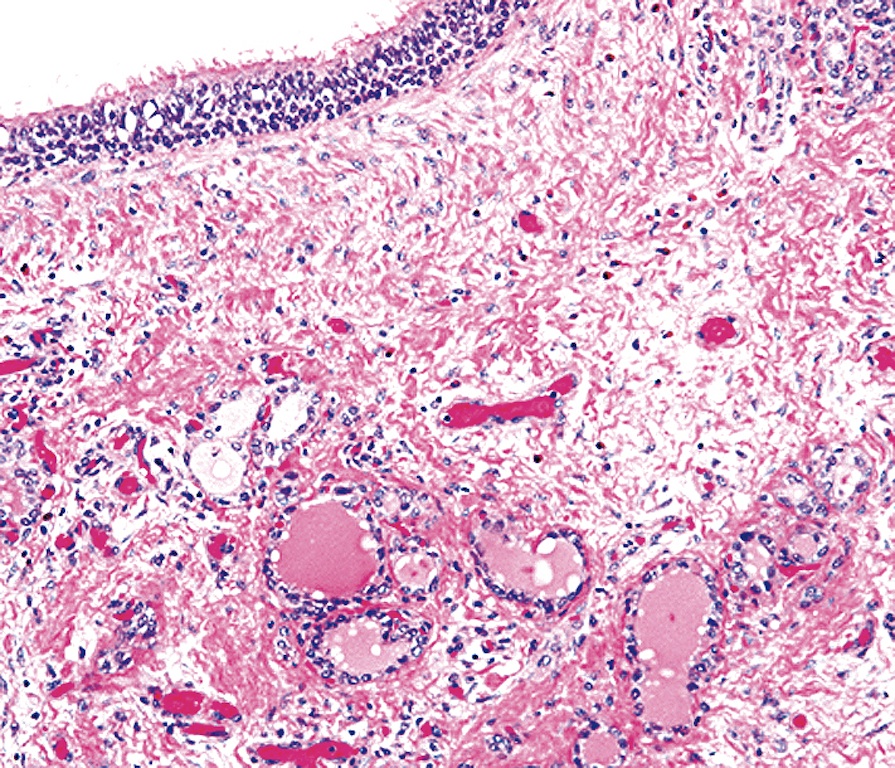

Microscopic (histologic) description

- Type of epithelial lining varies by site, and combinations of the types below can be seen in a single cyst (Head Neck Pathol 2013;7:50):

- Ciliated pseudostratified columnar (respiratory) epithelium in lower neck, perhaps due to its close proximity to upper respiratory tract

- Nonkeratinizing squamous epithelium in higher neck (near tongue and foramen cecum), also can be of metaplastic origin in inflammatory settings

- Stratified cuboidal epithelium at level of hyoid bone

- Very often the cyst is denuded of epithelium, at least focally, which reflects epithelial damage by inflammation

- Secondary inflammation is common, especially in sinus tract (J Pediatr Surg 1984;19:506):

- Intense lymphocytic infiltration, rarely arranged into lymphoid follicles

- Admixture of neutrophils (if the cyst is infected)

- Granulation tissue and fibrosis

- Thyroid follicles in the cyst / duct wall:

- Found in 30% - 60%, with higher yield on serial sections

- Seen in small irregular groups

- Thyroid epithelium may be normal or rarely hyperplastic or neoplastic

- Thyroid tissue often hidden by inflammation (Laryngoscope 2001;111:1002)

- Absence of thyroid tissue does not exclude the diagnosis of TGD cyst

- Mucous salivary-type glands can be found in the cyst wall, frequently in lingual and suprahyoid locations (Ann Otol Rhinol Laryngol 1996;105:996)

Microscopic (histologic) images

Contributed by Andrey Bychkov, M.D., Ph.D., Mark R. Wick, M.D. and AFIP